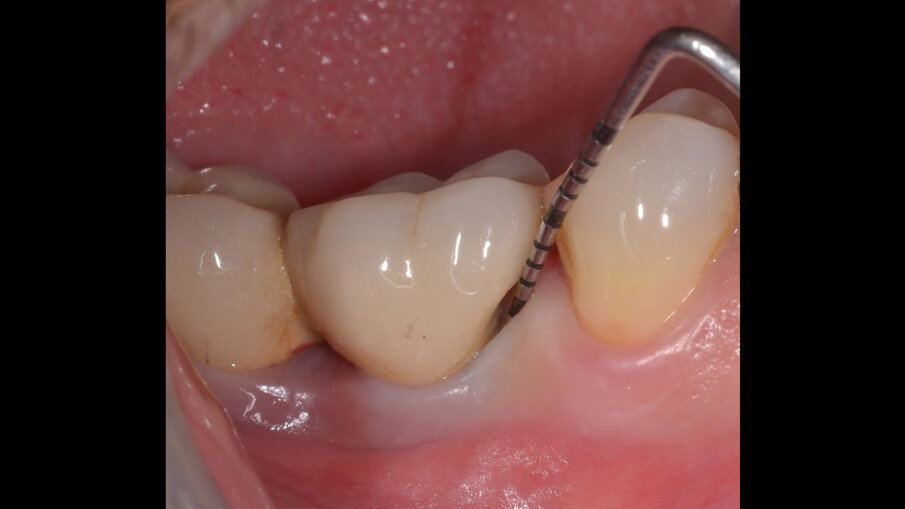

Il paziente, di sesso maschile e di 48 anni di età, è in buone condizioni di salute generale ma, a distanza di 10 anni dall’inserimento, presenta due impianti endossei, in posizione 4.6 e 4.7 con uniforme perdita ossea e con sondaggi di profondità variabile tra 6 e 9 mm accompagnati da sanguinamento, con tessuti marginali che mostrano importanti aspetti infiammatori, causa di sintomatologia dolorosa per il paziente (Figg. 1a-f).

I siti interessati sono stati strumentati per via non chirurgica, utilizzando strumenti manuali, strumenti ultrasonici e air polishing con eritritolo. Al termine della seduta è stato applicato il gel di ozono (Ozosan Gel - Bioactiva) all’interno delle tasche, lasciando agire il dispositivo per 8 minuti, quindi eseguendo lavaggio con soluzione fisiologica. Il post-operatorio ha avuto un decorso privo di dolore con rapida remissione della sintomatologia soggettiva. Il paziente è stato inserito in un programma di mantenimento parodontale trimestrale. A distanza di 6 mesi dal trattamento non chirurgico della perimplantite, i siti si presentano stabili con profondità di sondaggio ridotta tra i 3 e i 5 mm con assenza completa di sanguinamento al sondaggio (Figg. 1g-m).